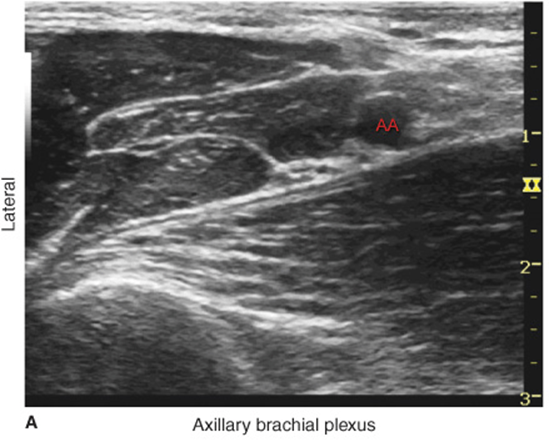

FIGURE 32-2. Cross-sectional anatomy of the axillary fossa and the transducer position to image the brachial plexus. The brachial plexus (BP) is seen scattered around the axillary artery and enclosed in the adipose tissue compartment containing BP, axillary artery (AA), and axillary vein (AV). MCN, musculocutaneous nerve.

With the patient in the proper position, the skin is disinfected and the transducer is positioned in the short axis orientation to identify the axillary artery (Figure 32-4A about 1 to 3 cm from the skin surface. Once the artery is identified, an attempt is made to identify the hyperechoic median, ulnar, and radial nerves (Figure 32-4B). However, these may not be always well seen on an ultrasound image. Frequently present, a reverberation artifact deep to the artery is often misinterpreted for the radial nerve. Pre-scanning should also reveal the position of the musculocutaneous nerve, in the plane between the coracobrachialis and biceps muscles (a slight proximal-distal movement of the transducer is often required to bring this nerve into view) (Figure 32-5).

FIGURE 32-4. (A,B) Median (MN), ulnar (UN), and radial (RN) nerves are seen scattered around the axillary artery with the tissue sheath (white-appearing tissue fasciae around the artery) containing nerves and axillary vessels. The musculocutaneous nerve (MCN) is seen between the biceps and coracobrachialis (CBM) away from the rest of the brachial plexus. AA, axillary artery.